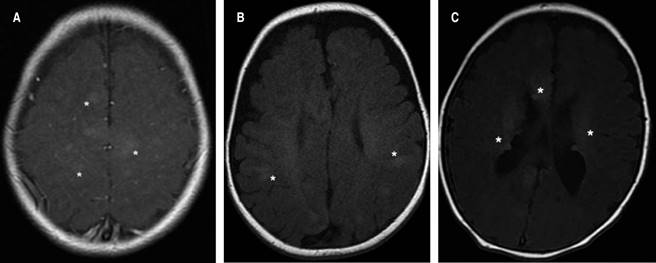

Las manifestaciones neurológicas son la principal causa de morbilidad y mortalidad en pacientes con CET, incluyendo las displasias corticales, las cuales se definen como trastornos de la migración neuronal durante el desarrollo embrionario. De los pacientes aquí reportados, la mayoría presentó hamartomas glioneuronales corticales, nódulos subependimarios o líneas de migración radial en la sustancia blanca (Figura 2).20

Figura 2: Imágenes de las alteraciones a nivel del sistema nervioso central en el complejo esclerosis tuberosa, señaladas por los asteriscos: A) Túberes corticales multifocales. B) Líneas de migración radial en la sustancia blanca. C) Nódulos subependimarios calcificados.

Con respecto al SEGA, los presentan de 5-20% de los pacientes con CET; son tumores benignos, de crecimiento lento que surgen en el área periventricular.6,21 Su detección suele ser después de la segunda década de la vida, causando compromiso neurológico grave, incluyendo hidrocefalia obstructiva, por lo cual se recomienda realizar estudios de imagen de resonancia magnética (IRM) de manera anual o cada tres años; ninguno de los pacientes en esta serie lo presentaron. Por otro lado, con IRM también es posible encontrar lesiones en la sustancia blanca como nódulos, quistes y áreas de gliosis e hipomielinización.22